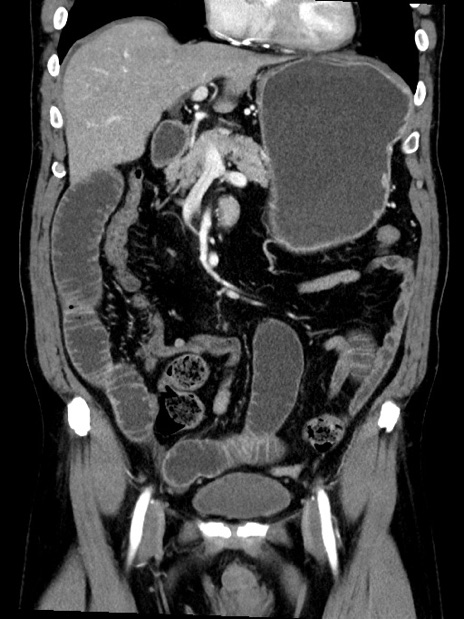

症例35(冠状断像)

【症例】70歳代 男性

【主訴】腹部膨満、嘔吐

【現病歴】昨日より腹部膨満感出現。本日増悪し、仙痛出現。嘔吐あり、受診。

【既往歴】糖尿病、胆摘後

【身体所見】BP 149/80mmHg、HR 74/min、BT 35.9℃、腹部:膨満、軟、圧痛なし。腸雑音減弱あり。上腹部正中切開瘢痕あり。

【データ】WBC 13500、CRP 1.72